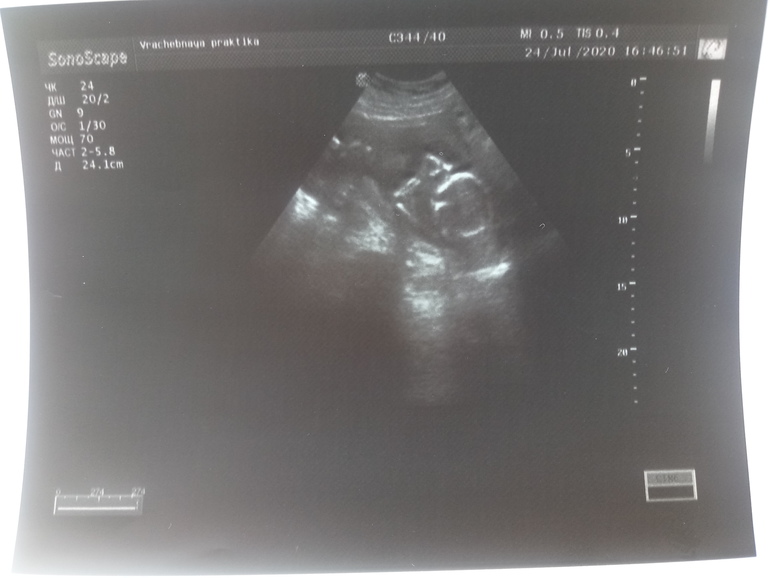

Так неожиданно добрались мы уже до пятого месяца. Скоро уже половина будет, а я все никак не могу привыкнуть к тому, что внутри меня наконец-то живет наш маленький любимый человечек. Вчера наконец-то получилось попасть с мужем на узи, мне было важно, чтобы он тоже увидел это чудо. В итоге малыш и ручками ему махал, и ротиком что-то делал, мне только кулачками пытался куда-то бить😂.